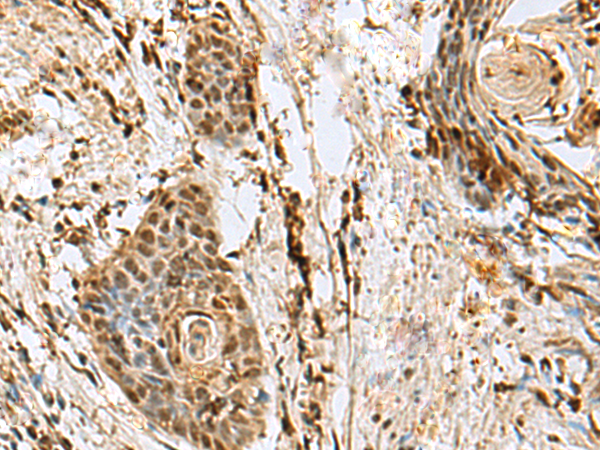

ELISA, IHC |

IHC positive control: |

Human thyroid cancer |

IHC Recommend dilution: |

50-300 |